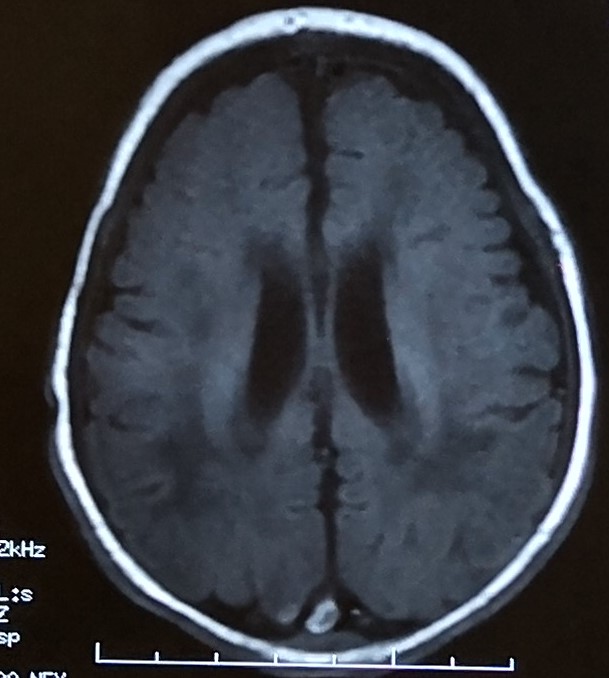

(2)临产后:经审阅提供的胎心监护图,3月2日7:00-8:00胎心基线无变异;12:20-12:40胎心基线无变异。21:10宫口开全,胎心重度变异减速,证实胎儿宫内窘迫,此时已进入第二产程,院方应立即助产尽快终止妊娠,但直至21:30胎儿才娩出,第二产程中胎儿窘迫达20分钟以上,最终出生后证实其存在新生儿重度窒息、缺血缺氧性脑病等。我们认为院方在被鉴定人宫口开全后未及时助产尽快终止妊娠,加重了胎儿窘迫,其上述行为存在医疗过错。另外,需要指出的是,被鉴定人于3月2日16:00临产,21:10宫口开全,但送审材料中缺少被鉴定人于19:25至21:10此关键时段的胎心监护图,结合21:10胎心重度变异减速,故不排除被鉴定人在19:25至21:10已经存在胎儿宫内窘迫的情况,我们认为院方上述行为不符合诊疗原则、存在医疗过错。(3)单脐动脉问题:被鉴定人经产前检查证实其胎儿单脐动脉,出生后胎儿体重3850g。经检查未发现身体畸形。单脐动脉可能会导致胎儿宫内缺氧,故院方在被鉴定人单脐动脉合并产前多次胎心监护异常的情况下,更应予以足够的注意义务、考虑到胎儿宫内缺氧可能并应尽快终止妊娠。...(5)胎盘性状问题:送审材料中记载被鉴定人莫平莉为球状胎盘。从提供的录像上来看,可见脐带偏心附着,但不能仅凭此录像确定为球状胎盘。球状胎盘对母胎一般无太大影响,被鉴定人即使存在球状胎盘,该问题亦不是导致新生儿重度窒息的主要原因。3.因果关系分析:被鉴定人于2018年4月19日最后一次在上级医院出院,4月25日在家中死亡,其死亡后未进行尸体解剖检验,准确判断其死亡原因存在一定困难。但就本案来讲,被鉴定人出生后即为重度窒息,存在缺氧缺血性脑病、肺炎、呼吸衰竭、代谢性酸中毒并多器脏受损等多种严重损害后果,后又并发脑萎缩、癫痫、纳奶少,虽在上级医院先后两次住院治疗,因其脑缺氧并发症及后遗症严重,后期恢复健康的可能性基本没有。根据被鉴定人的诊疗过程及病情发展变化情况,可以认定被鉴定人死亡应与其重度窒息导致的缺血缺氧性脑病、脑萎缩、癫痫、多脏器功能损害等有明确的因果关系。因北京某医院在对被鉴定人诊疗过程中存在多处过错,未能及时终止妊娠,延误其胎儿窘迫的及时治疗,从而导致被鉴定人重度窒息及缺血缺氧性脑病等,最终死亡。故我们认为北京某医院医疗过错与被鉴定人死亡之间存在因果关系。本例医疗过错的责任程度以同等责任为宜。